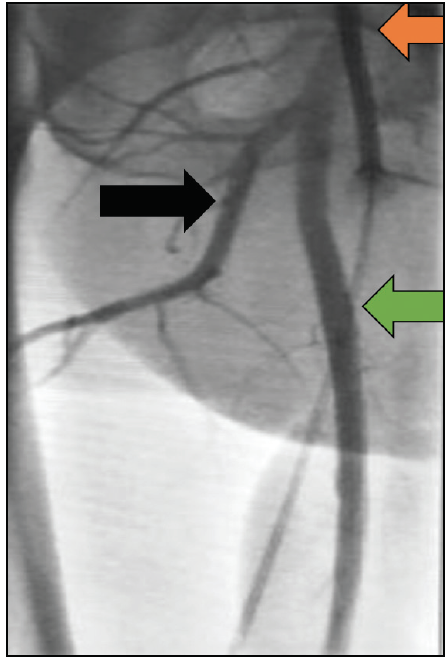

External Ipsilateral Bypass Circuit

Another alternative strategy utilizes the side arm of the large-bore occlusive sheath to create an ipsilateral bypass circuit. A 4- to 6-F short sheath is inserted in the ipsilateral SFA in an antegrade fashion. The side arm of the ipsilateral antegrade sheath can then be connected via a male-to-male connector to the side arm of the large-bore occlusive sheath, constituting an ipsilateral bypass circuit that provides adequate perfusion to the lower limb. When using this strategy with an Impella device, the repositioning sheath must not be advanced into the Impella 14-F sheath to avoid occlusion of the side arm that is now providing perfusion (Figure 5). Management of this conduit follows the same protocol as previously outlined for the contralateral bypass technique. The advantage of this strategy is that it does not require contralateral arterial access.

Figure 5. Left common femoral artery with occlusive Impella 14-F sheath in situ. To maintain flow to the left leg, a bypass circuit was created. A 6-F sheath was used to access the left common femoral artery in an antegrade puncture position distal to the large sheath. The side arm of the 6-F sheath was connected to the large sheath using a male-to-male connector, creating flow (dotted arrow).